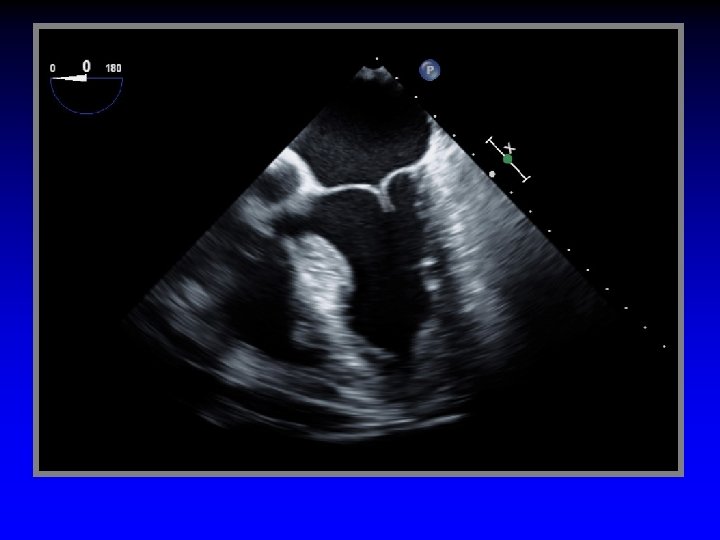

Inter-commissural distance Aorta Septo-Lateral distance Tent Vol Coapt Displ Tenting Height Coaptation length

Leaflet Overlap

Tenting area Coaptation depth Leaflet overlap